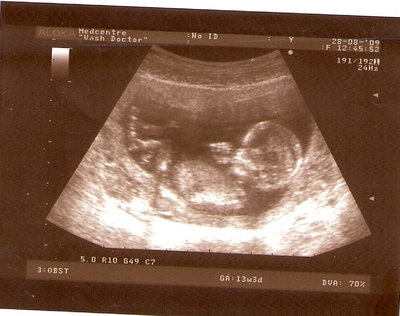

13 НЕД И 5 ДНЕЙ

| Вложения: |

3.jpg [ 96.81 КБ | Просмотров: 2809 ]

Nikisa писал(а): Foto prosto chudesnoe. A na kakom sroke uznali, chto sin.............. НА 13 НЕДЕЛЯХ.КАК РАЗ ВОТ В ЭТО узи, ОНО УМЕНЯ ВТОРОЕ БЫЛО. ЭТО КОНЕЧНО МАЛЕНЬКИЙ СРОК ДЛЯ ОПРЕДЕЛЕНИЯ ПОЛА. НО Я ПОПРОСИЛА ВРАЧА(ЭТО КТСТАТИВ РОССИИ БЫЛО) ХОТЯ БЫ ПРЕДПОЛОЖИТЬ. ЕЙ ВСЁ ТАКИ УДАЛОСЬ РАССМОТРЕТЬ.НУ ВООБЩЕМ ЧЕРЕЗ НЕСКОЛЬ ДНЕЙ ПОЙДУ К ВРАЧУ, УЖЕ АМЕРЕКАНСКОМУ И УЗНАЮ ТОЧНО. К ТОМУ ВРЕМЕНИ У МЕНЯ БУДЕТ СРОК 18 НЕДЕЛЬ. ХОТЕЛОСЬ БЫ ПОСМОТРЕТЬ НА ДРУГИЕ ФОТО НА ЭТОМ СРОКЕ ИЛИ БОЛЬШЕ. ТАК ЧТО ВЫКЛАДЫВАЙТЕ, ЕСЛИ НЕ ЖАЛКО!